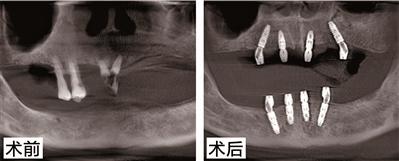

陳伯今年76歲了,也是德國種植牙技術(shù)的親身體驗(yàn)者之一。他之前患有牙周病,牙齒全口缺失,在醫(yī)生的指導(dǎo)下采用了德系A(chǔ)ll-on-N種植技術(shù)和種植技術(shù),種牙到現(xiàn)在3年了,牙齒依然堅(jiān)固如初。為此,陳伯感嘆道:“缺牙這么多年,沒想到是柏德幫自己實(shí)現(xiàn)了多年的愿望。我記得種完牙當(dāng)天就能正常吃飯。一把年紀(jì)還能再次享受口福,這種感覺真好?!睋?jù)悉,百蟹宴當(dāng)天,陳伯將應(yīng)邀分享種牙感受,并與現(xiàn)場(chǎng)觀眾比拼吃大閘蟹,展示種牙后的果。種植牙PK大閘蟹,究竟誰能勝出呢,我們拭目以待!

針對(duì)陳伯的種牙情況,柏德口腔天河院長薛啟明表示,All-on-N種植技術(shù)和種植技術(shù)可以說能很好地解決多顆牙缺失或者全口無牙問題,尤其是對(duì)于上了年紀(jì)又怕痛的缺牙患者。電腦三維模擬成像技術(shù)能在手術(shù)前,地計(jì)算種植點(diǎn)位、植入角度和深度,再通過3D種植導(dǎo)板植入,避開神經(jīng)系統(tǒng)和血管,實(shí)現(xiàn)種植。整個(gè)手術(shù),在麻醉儀的幫助下,患者幾乎沒有任何不適。德系A(chǔ)ll-on-N種植技術(shù)還有一個(gè)好處就是,只需要花少量的錢,就能恢復(fù)整口牙的咬合果,這對(duì)患者來說無疑是實(shí)惠的。